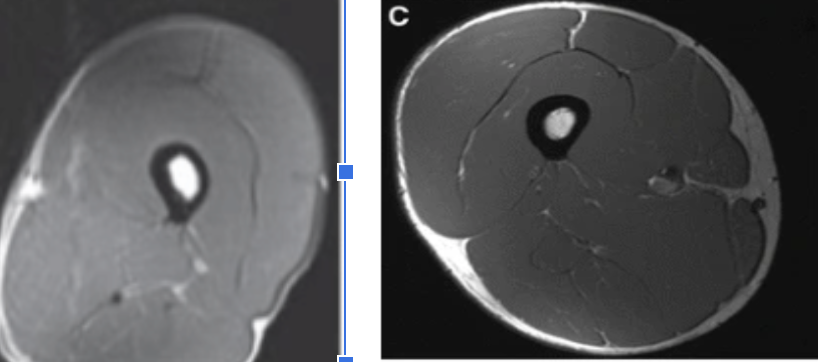

Next, compare that same 74 y.o. sedentary man (left) to a 74 y.o who is highly active (right)

The difference in muscle mass, bone density and fat deposits are undeniable despite the similar age.

Muscle mass is “use it or lose it” and one is deconditioned, the other active. x.com

The difference in muscle mass, bone density and fat deposits are undeniable despite the similar age.

Muscle mass is “use it or lose it” and one is deconditioned, the other active. x.com

Finally, compare the 74 year old highly active man to the young, healthy 24 year old. In this case, it’s not even clear who’s thigh we are looking at in each picture.

There’s no drug on the planet as potent for anti-aging than resistance training.

And it’s never too late.. x.com

There’s no drug on the planet as potent for anti-aging than resistance training.

And it’s never too late.. x.com